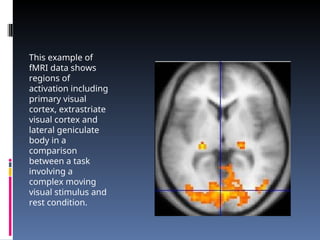

This example of

fMRI data shows

regions of

activation including

primary visual

cortex, extrastriate

visual cortex and

lateral geniculate

body in a

comparison

between a task

involving a

complex moving

visual stimulus and

rest condition.